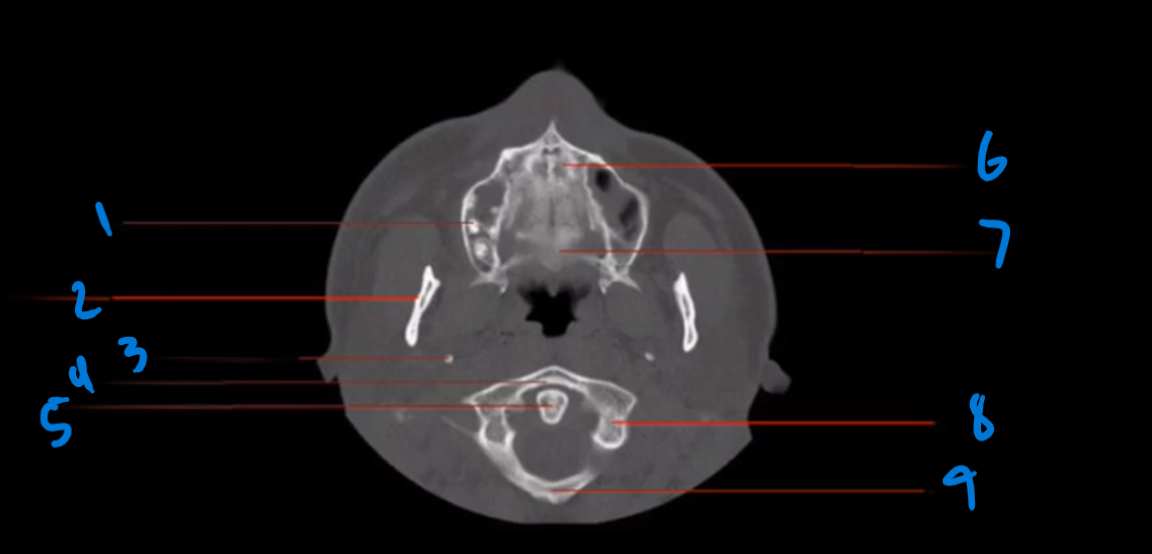

Landmark 1

Lacrimal Duct

Landmark 2

Maxillary Sinus

Landmark 3

Lateral Pterygoid Process

Landmark 4

Mandible

Landmark 5

Mastoid Air Cells

Landmark 6

Pony tail

Landmark 7

Maxilla

Landmark 8

Deviated Nasal Septum

Landmark 9

Medial pterygoid Process

Landmark 10

Landmark 11

Occipital Condyle

12

Foramen Magnum